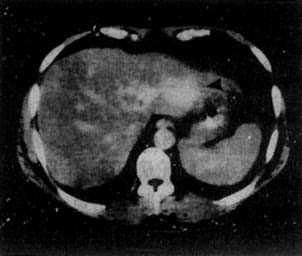

肝血管瘤是一种较为常见的肝脏良性肿瘤,临床上以海绵状血管瘤最多见,自然人群尸检发现率为0.35-7.3%,占肝良性肿瘤的5-20%。近年来,随着人们健康体检的意识提高及各种影像诊断技术的进步,无症状的小血管瘤发现率明显升高。多数病例临床无症状或症状轻微,病程长、生长缓慢,预后良好。目前对该病的基础和临床研究不多,缺乏成熟而严格的诊治标准,治疗方案。

4.肝血管瘤B超结果多显现为瘤体较大者能够看到其中的网状构造,瘤体较小者则多为强光团;而肝癌时B超结果多显现为边境较为分明的强光团或暗区,且在其四周尚可见一圈典型的声晕。